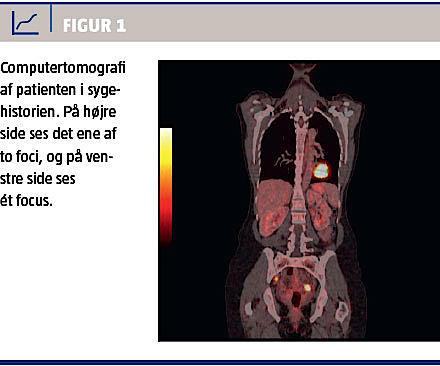

Patienten blev henvist til en gynækologisk udredning. Man bestilte CA-125-måling, magnetisk resonans (MR)-skanning af columna totalis, computertomografi (CT) af thorax og abdomen samt gynækologisk undersøgelse med vaginal ultralyd (UL)-skanning. Den gynækologiske undersøgelse og den vaginale UL-skanning viste normale forhold, CA-125-koncentrationen var let forhøjet på 77 arbejdsenheder/ml. MR-skanning og CT viste som eneste fund diskret forstørret venstre ovarium. Man supplerede med positronemissionstomografi (PET)-CT, der viste tre små foci i bækkenet med øget fluordeoxyglukoseoptagelse (Figur 1). Patienten blev henvist til et center med gynækologisk-onkologisk ekspertise pga. mistanke om primær ovariecancer. Ved eksplorativ laparotomi fandt man makroskopisk normale forhold, men pga. fund på PET-CT blev der foretaget bilateral salpingo-ooforektomi, omentektomi og radikal excision af lymfeknuder i bækkenet. Det endelige patologisvar viste primær tubacancer af typen serøst adenokarcinom med spredning til begge ovarier og til ingvinal lymfeknude. Patienten havde således primær tubacancer i stadium IIIC.

PET-CT var afgørende for diagnosen. Undersøgelsen gjorde det muligt at lokalisere de tre foci, der viste sig at være primærcancer, og patienten blev herefter radikalt opereret. I dag bruges PET-CT ved udredning for ovarie- og tubacancer på alle fem gynækologiske cancercentre. Sygehistorien illustrerer betydningen af PET-CT i den primære udredning for gynækologisk cancer. Flere studier har vist, at PET-CT har en højere sensitivitet og specificitet end CT alene ved diagnosticering af både primær ovariecancer og recidiv af ovariecancer [4, 5]. Endvidere giver PET-CT en mere præcis anatomisk lokalisation og har en øget sensitivitet og specificitet ved fund af lymfeknudemetastaser end CT og PET alene. Dette kan have afgørende betydning for det videre behandlingsforløb [5].